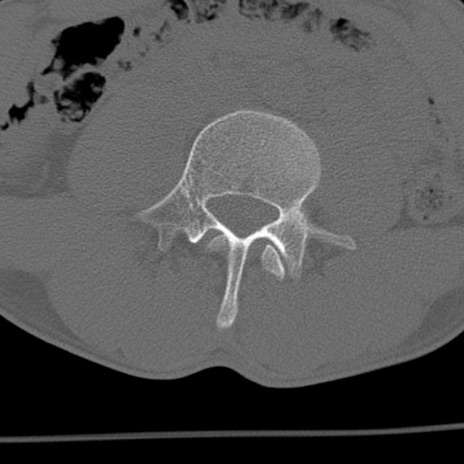

症例3 腰椎CT(横断像)

腰椎CT